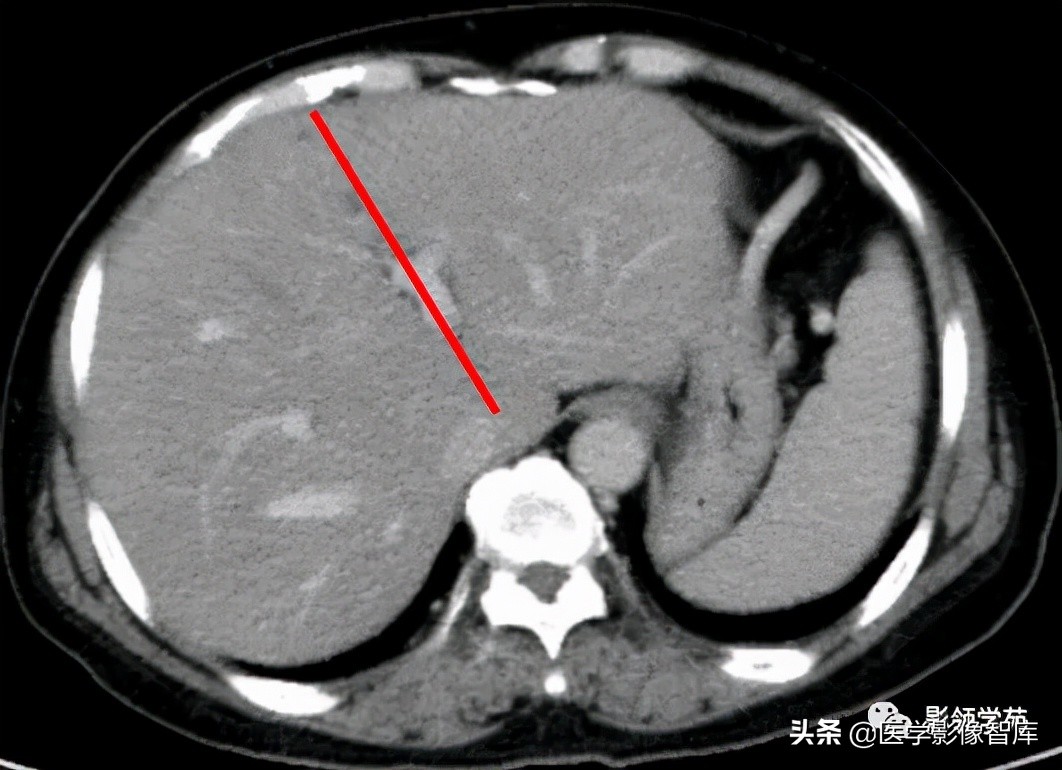

1、正中裂:下腔静脉 左前缘与其右前方的肝中静脉长轴的连线。

将肝分为左、右半肝。裂中有肝中静脉走行。

2、左叶间裂:又称脐裂,镰状韧带左侧1cm处至下腔静脉左侧的连线,于人体正中线前方偏右约15°;把左半肝为左内叶与左外叶;裂中有肝左静脉走行。

第一肝门层面CT横断面解剖